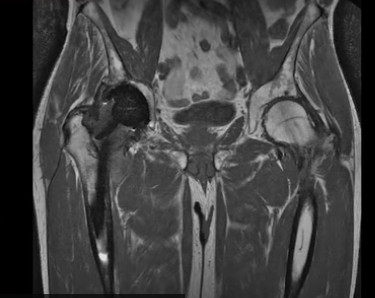

고관절 수술부위가 금속때문에 까맣게 보이기도 합니다.